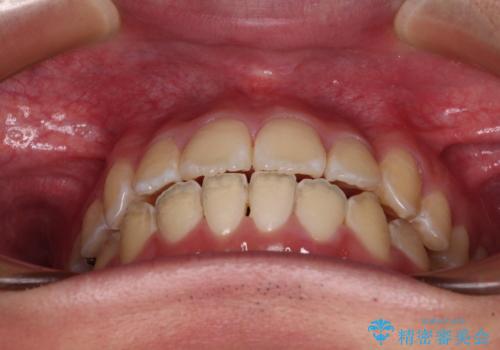

- 上下前歯のデコボコを気にして来院された患者様です。

ワイヤー矯正でもマウスピース矯正でも可能でしたが、短期間で、自身の手を煩わせることなく治療を行いたいとのことで、ワイヤー装置にて矯正治療を行うこととしました。

当初予定通り、1年間で治療を終えることができました。